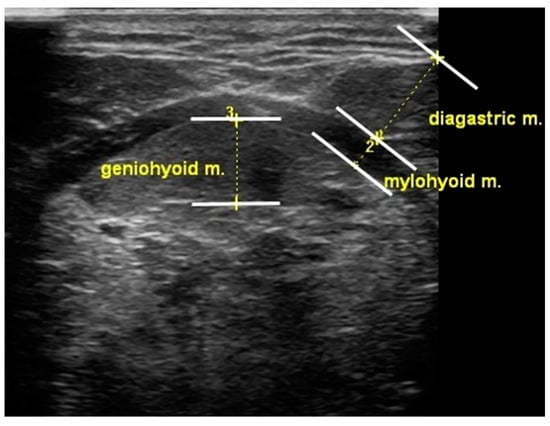

In this study, tongue and suprahyoid muscle thickness was measured using a portable ultrasonography device (SONON300L, Healcerion, Seoul, Korea) with a 10 MHz and linear- and convex-array transducer. Change in tongue thickness was determined by measuring the distance between the upper and lower surfaces of the tongue muscles in the center of the plane perpendicular to the Frankfort horizontal plane of the frontal session. The vertical distance was measured from the surface of the mylohyoid muscle to the dorsum of the tongue. The digastric muscle measurements were obtained from the upper to the lower boundary of the fascia covering the muscle at the broadest point perpendicular to the mylohyoid muscle. The mylohyoid muscle measurements were recorded below the measurement point of the digastric muscle, from the upper to the lower boundary of the fascia covering the muscle (Figure 2). A blinded investigator (rehabilitation physician) measured and analyzed the muscle thickness using ultrasound.

Figure 2. Measurement of oropharyngeal muscle thickness.